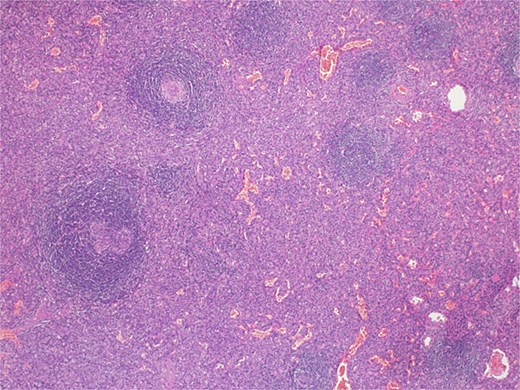

The patient underwent laparotomy for a planned excision of retroperitoneal mass as if it was a sarcoma. A temporary bilateral ureteral stent was placed. The mass was extending up from the right side of the retroperitoneal abdomen all the way to the right iliac fossa and pelvis. The mass was adherent to the common iliac artery and external iliac artery. Dissection was carried out using sharp and blunt dissection as well as the Harmonic scalpel. The blood supply from the external iliac artery was ligated and venous drain was sutured ligated. Because multiple large pedunculated fibroids (measuring 8 × 7 cm the largest, and the second one was 5 × 5 cm, there was one 3 × 3 cm, there were another two smaller ones, measuring 3 × 2 cm and one small 1 cm), excision of the three largest fibroids facilitate for a complete excision of the retroperitoneal mass (Fig. 4) and was sent for histopathology, which exhibited retroperitoneal AS (Fig. 5) negative for malignancy. The patient had an uneventful hospital course and was discharged 1 week later.

Microscopic examination picture confirmed the splenic tissue that included white and red pulps (hematoxylin & eosin stain 40×).